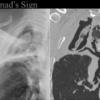

Monad's sign

Aspergilloma